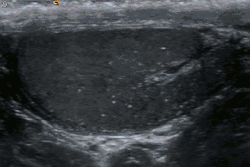

Testicular microlithiasis is an unusual condition diagnosed on testicular ultrasound. It is believed to be found in 0.1–0.6% of males globally, with frequency varying based on geographic location and is more often found in individuals with subfertility. It is often an asymptomatic, non-progressive disease; though in a very small number of cases it may also cause bouts of extreme chronic fatigue, hormone imbalance and pain, which can be severe and accompanied by swelling around the testicular region (dependent on the size and location of the calcification). In an extremely rare select few cases, individuals with microlithiasis have also been known to experience calcification of the prostate, which can lead to the passing of stones. These rare cases can lead to secondary infections if not treated with care, due to the resulting damaged tissue. However, these symptoms are rarely seen in the majority of people who have been diagnosed.

The cause is unknown, but this condition has been associated with testicular cancer in a small group of individuals, cryptorchidism, mumps, infertility and intraepithelial germ cell neoplasia. Classic testicular microlithiasis is defined as five or more echogenic foci per view in either or both testes, and limited testicular microlithiasis defined as one or more echogenic foci that do not satisfy the criteria for classic testicular microlithiasis. In 80% of cases, both testicles are affected.

Testicular ultrasound